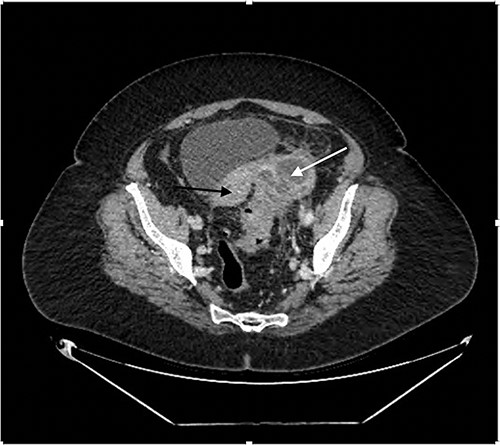

A 68-year-old woman presented to hospital with 1 month history of Left iliac fossa (LIF) pain and weight loss of 5 kg. She denied per vaginal (PV) discharge and urinary symptoms, and had no medical background nor a history of previous colonoscopies. On examination, she was haemodynamically stable, not in respiratory distress and was afebrile at 36.8°C. The patient demonstrated LIF tenderness but was not peritonitc. Laboratory results were significant for increased C-reactive Protein (CRP) of 185 mg/L, with normal white cell count (WCC) and normal tumour markers. Contrast enhanced computed tomography (CT) Abdomen/Pelvis, illustrated in Fig. 1, demonstrated a LIF mass measuring 3.9 cm × 3.4 cm × 2.9 cm in the area of the left ovary, abutting the sigmoid colon, containing both solid and cystic components, with appearances inconclusive for ovarian neoplasia or pericolic abscess. There was evidence of sigmoid diverticulosis without diverticulitis.

Contrast enhanced CT Abdomen/Pelvis demonstrating mixed cystic/solid LIF mass (white arrow) adherent to the sigmoid colon and uterus (black arrow).